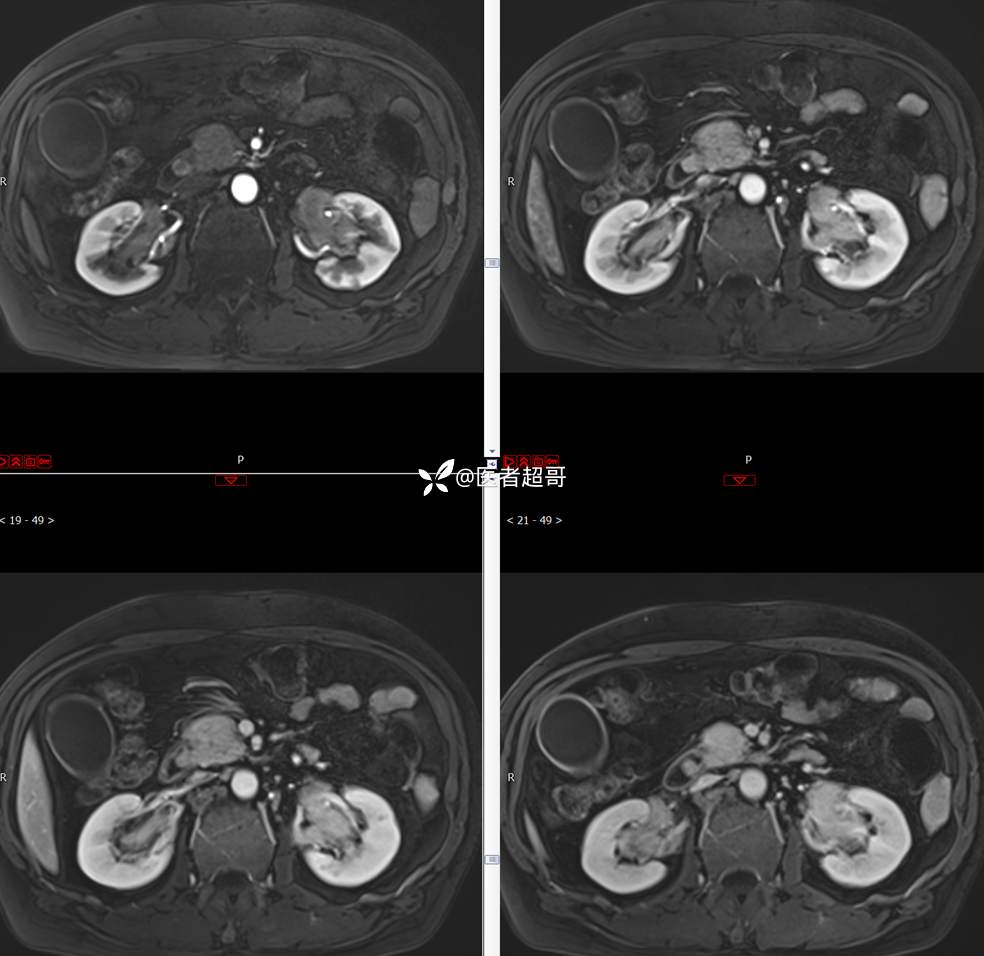

【影诊笔记772】腹痛就诊,发现肾脏病变,CT、MRI齐全,请高诊!

男,63岁 0200825 01

主 诉:间断腹痛15天

现病史:患者15天前无明显原因及诱因出现腹部疼痛不适,呈间断性钝痛,右下腹为著,无尿频、尿急、尿不尽,无发热、寒战,无腹胀。于市中心卫生院住院治疗,超声示:胰头低回声包块,胆系扩张,左肾囊肿,胆囊壁毛糙,胆囊内胆汁淤积。患者为求进一步诊治,遂以“肾盂肿瘤”收入院,患者自发病以来,神志清,精神可,饮食睡眠可,大便无明显异常,近期体重无明显增减。

既往史:既往体健